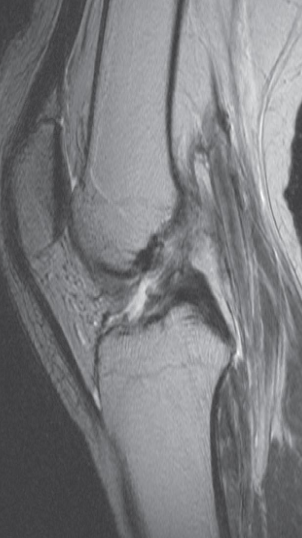

Imaging modality? MRI scan

Finding with a tear the anterior

Diagnosis Cruciate ligament (disrupted)

Imaging modality? Sagittal MRI through the medial part of the knee

joint

Finding tear in the posterior horn of the medial meniscus . The anterior horn appears normal.

Diagnosis the medial meniscus Tear